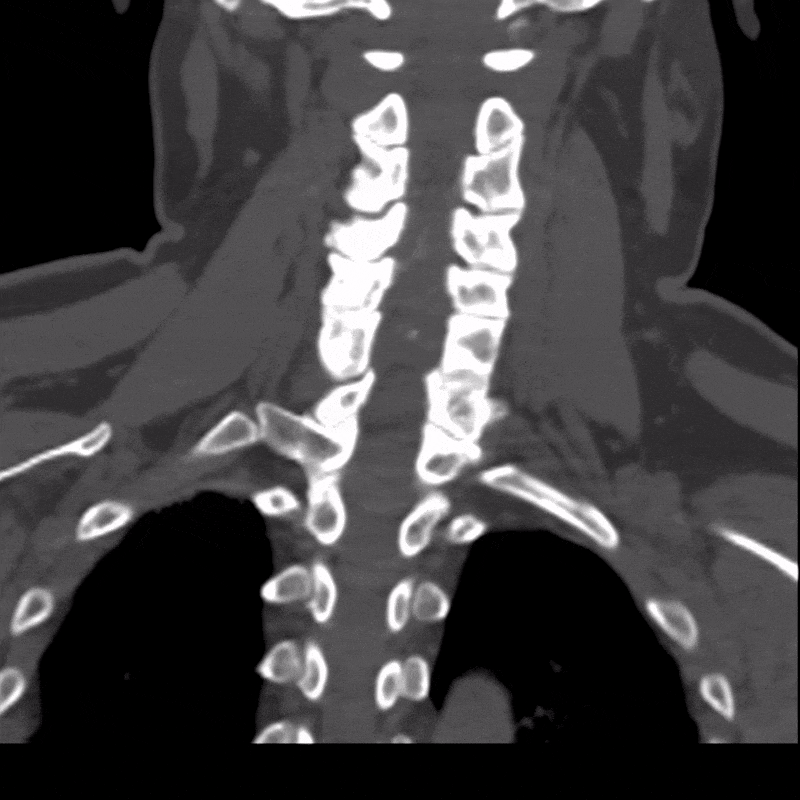

A CT scan of the cervical spine was obtained to further evaluate the presence and severity of OPLL. CT is well suited for this assessment because it clearly depicts bone and calcified structures, allowing the ossified ligament to be easily distinguished from surrounding soft tissues. The scan confirmed extensive OPLL from C2 through C6 with severe spinal canal stenosis.

Using the CT dataset, a radiologic technologist processed the images to create a series of advanced visualizations that highlight the distribution of ossification and its relationship to surrounding anatomy. These images provide different perspectives of the cervical spine and help translate cross-sectional findings into more intuitive views.

Figure B: 360-degree CPR view of the spinal canal. Learn more about CPRs here.